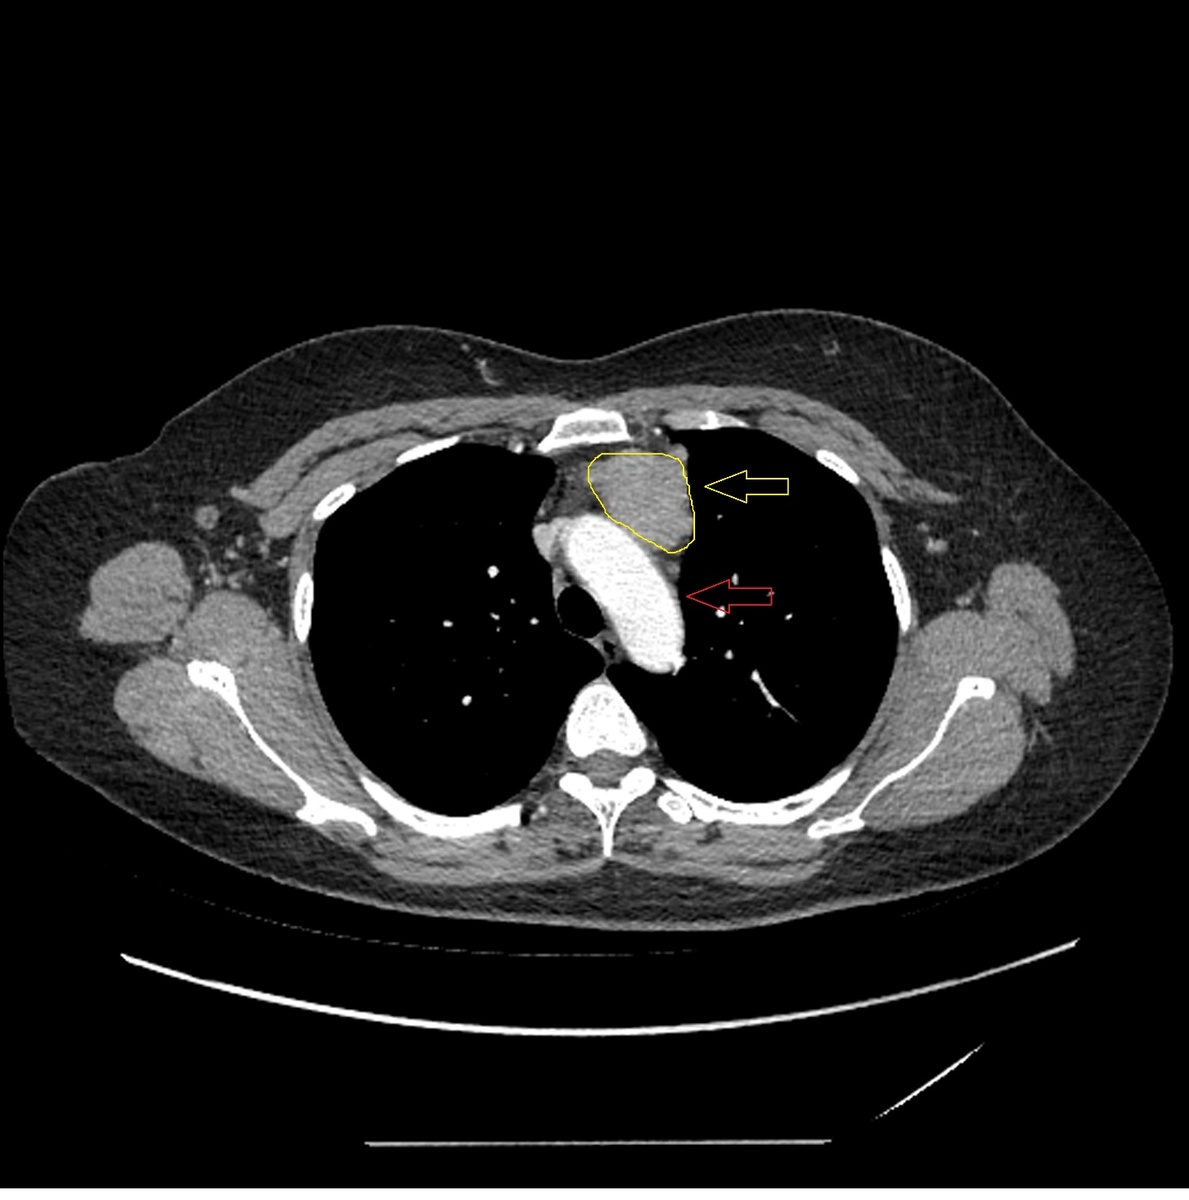

А вот изображение КТ ОГК этого же пациента. Тут диагностировать образование переднего средостения достаточно просто (опухоль выделена желтым цветом, аорта красной стрелкой).

КТ ОГК

Как вы можете убедится, по КТ ОГК проще диагностировать опухоль, чем через рентген.